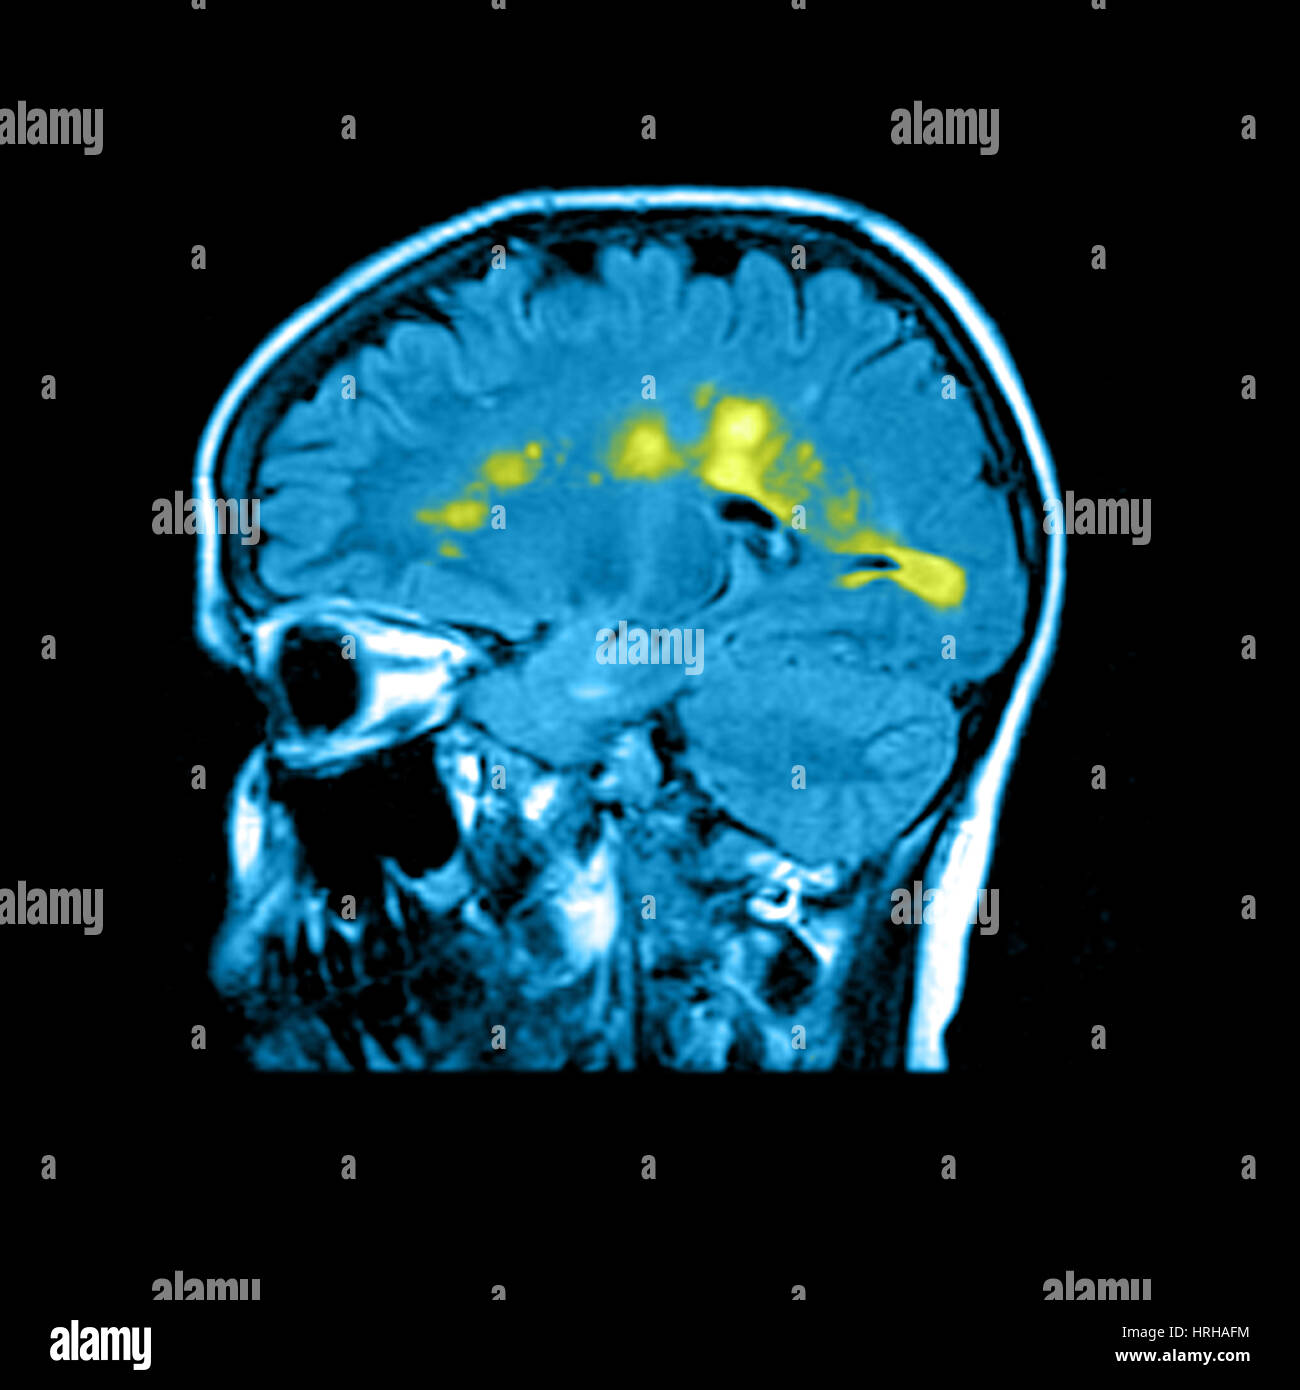

Brain MRI showing multiple sclerosis Stock Photo Alamy Multiple Sclerosis X Ray Findings the diagnosis of multiple sclerosis can be made if there is fulfillment of any of these five categories of criteria,. This article is an updated version of the 2013 article and focusses on the role of mri in. Mr offers by far the most sensitive technique for detecting multiple sclerosis (ms) lesions and has proved to be an important.. Multiple Sclerosis X Ray Findings.

MRI of Multiple Sclerosis Stock Photo Alamy Multiple Sclerosis X Ray Findings Mr offers by far the most sensitive technique for detecting multiple sclerosis (ms) lesions and has proved to be an important. This article is an updated version of the 2013 article and focusses on the role of mri in. radiology, along with a variety of tests, helps diagnose multiple sclerosis (ms). Multiple sclerosis (ms) is a chronic, inflammatory disease. Multiple Sclerosis X Ray Findings.